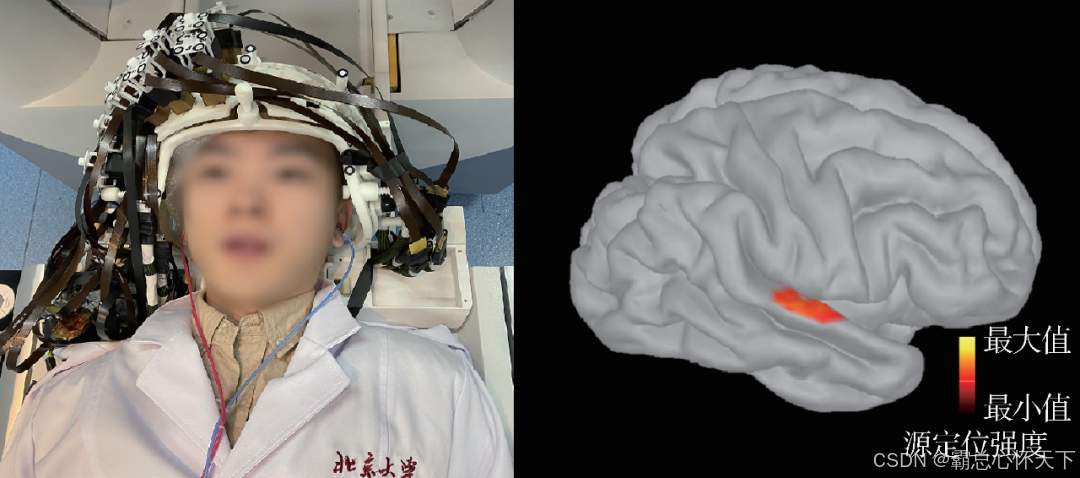

但是MEG不一样,它的通道就是要悬浮着的,后来我去查了MEG的采集操作图片,确实,通道是不贴脑袋的

假如我这里理解的有误的话,请大家积极指正,以免误人子弟,目前为止我还是这样认为的

5.compute source

选中文件夹右键,选择comput source

我这里采用Minimum norm imaging方法,sLORETA,选择了归一化,即constrained:Normal to cortex